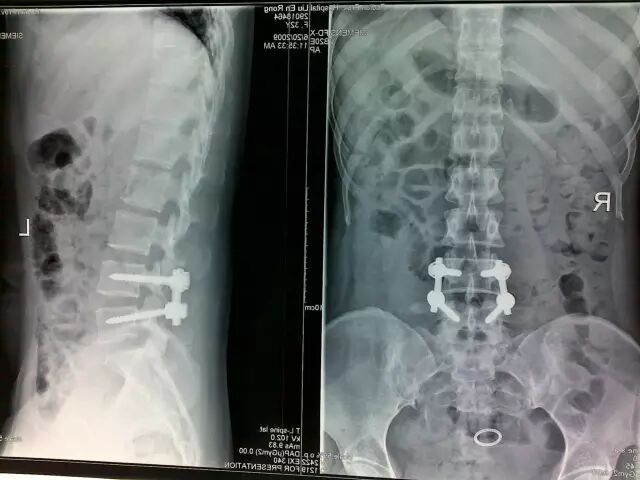

严重的腰椎间盘突出,脊髓受压明显,经过规范的保守治疗不能好转的,只能手术切除突出的椎间盘,解除神经压迫,稳定脊柱

术后